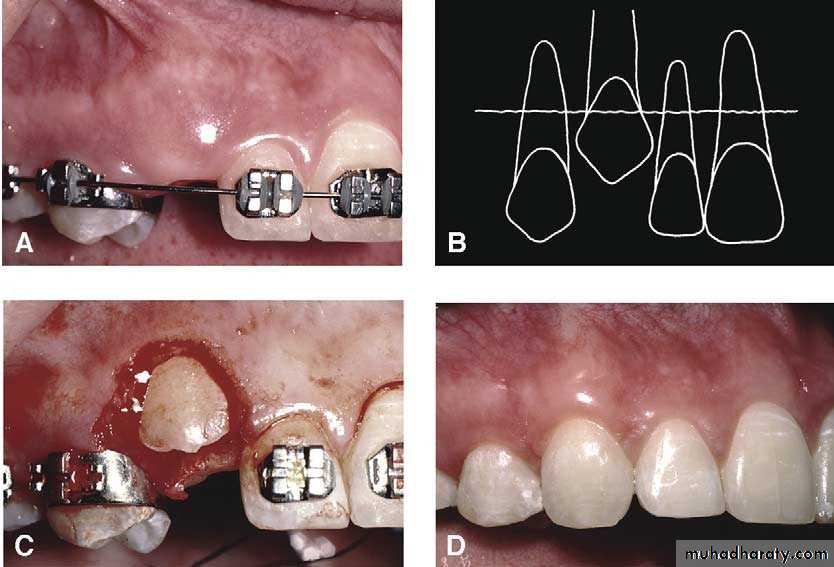

Surgical exposure with orthodontic traction: the path of eruption is obstructed

Surgical exposure with orthodontic treatment (palatal approach )